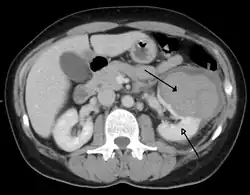

Kidneys

A large hematoma (closed arrow) of the left kidney (open arrow)

The kidneys may also be injured; they are somewhat but not completely protected by the ribs.[6] Kidney lacerations and contusions may also occur.[13] Kidney injury, a common finding in children with blunt abdominal trauma, may be associated with bloody urine.[13] Kidney lacerations may be associated with urinoma or leakage of urine into the abdomen.[4] A shattered kidney is one with multiple lacerations and an associated fragmentation of the kidney tissue.[4]